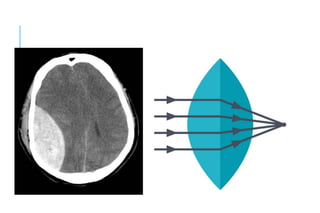

CT-SCAN

EDH

Bright/hyperdense

Biconvex in shape (lentiform), and has a well-

defined border that usually respects cranial suture

lines